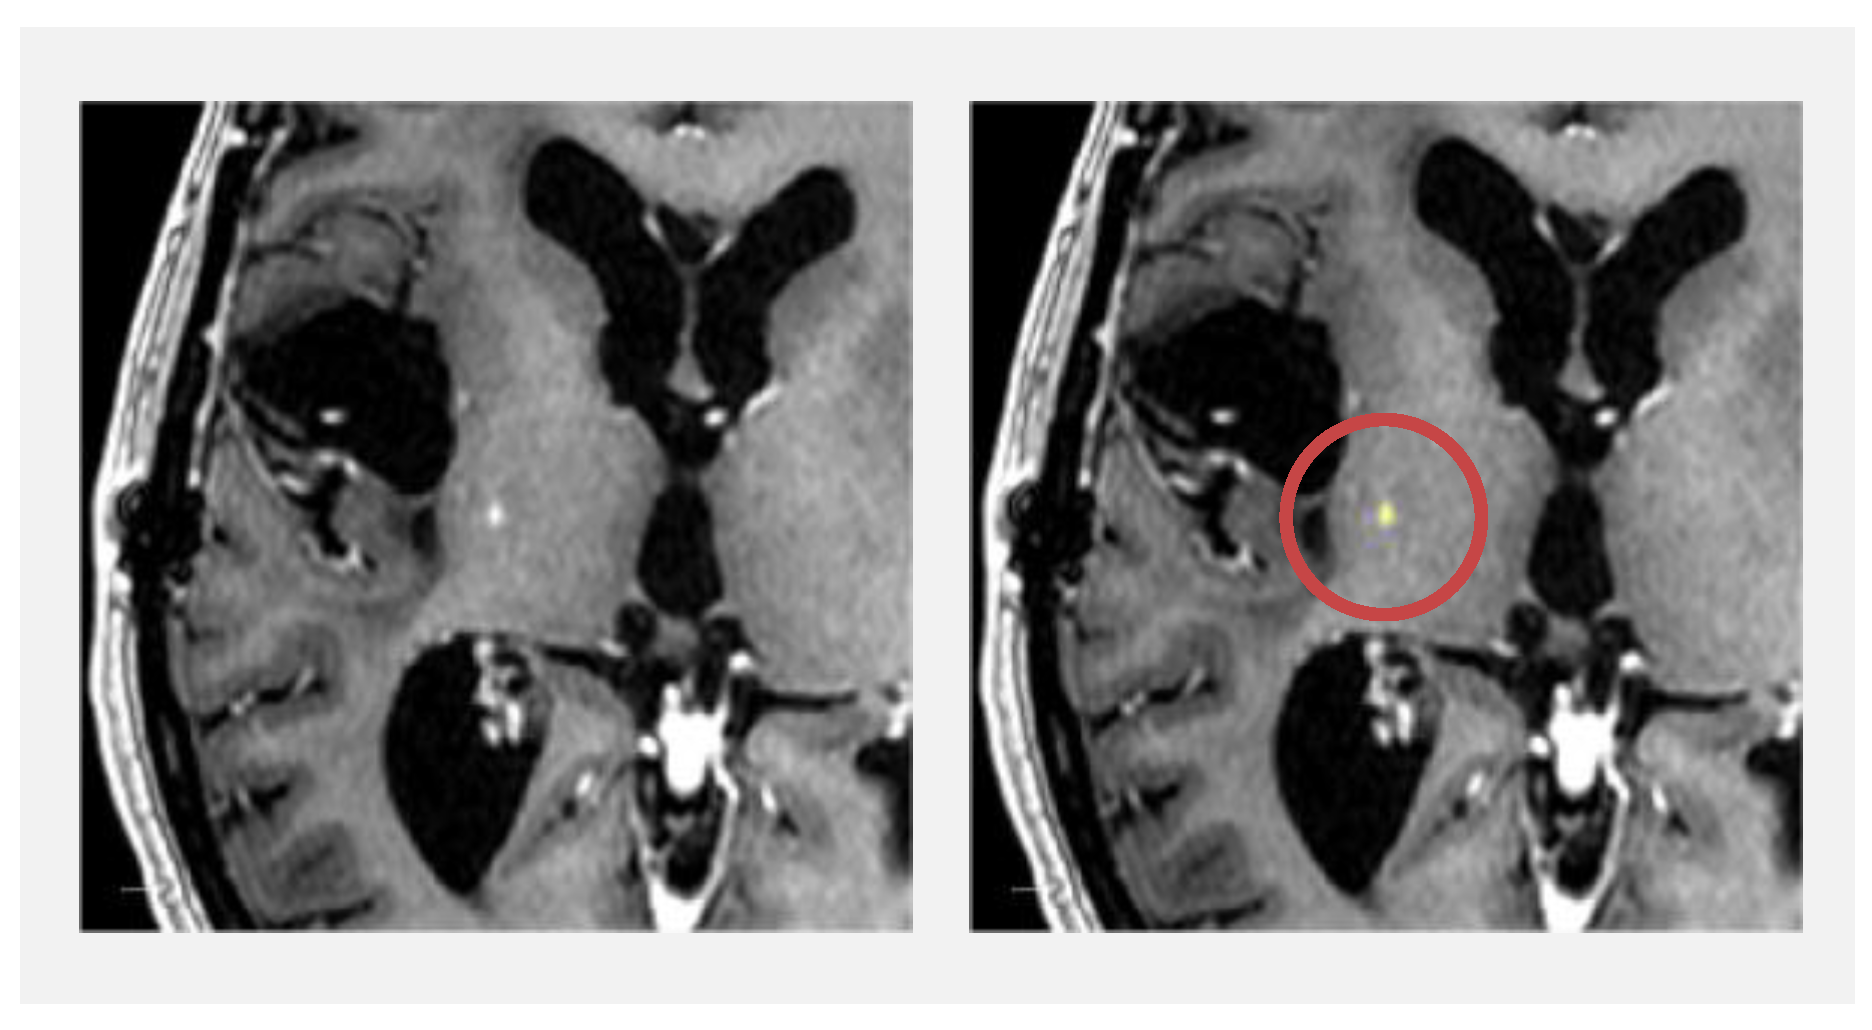

3.4.1. Contrast-Enhancing Tumour Lesions